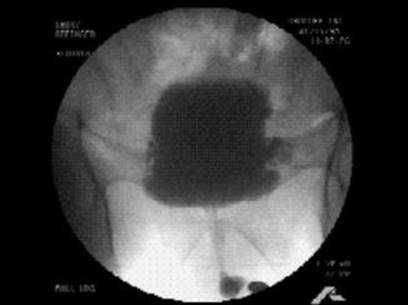

VUD can be seen in Figs. 11.2, 11.3, and 11.4. The patient initially demonstrated an involuntary detrusor contraction which caused incontinence while the patient’s sphincter was relaxed. With further filling, the patient was instructed to contract his sphincter when he sensed the involuntary detrusor contraction. The patient was able to successfully abort the contraction and prevent incontinence (Fig. 11.2).

Fig. 11.2

Case report—urodynamic tracing

Fig. 11.3

Filling phase

Fig. 11.4

Voiding phase

The VUD was also consistent with bladder outlet obstruction. He subsequently underwent an uncomplicated transurethral resection of his prostate (TURP). Postoperatively his flow rate increased to 28 mL/s (from 16 mL/s) on a voided volume of 360 mL and he was noted to have no residual urine. However, his OAB symptoms persisted after his TURP and he underwent a formal course of BT and PFMT. Bladder diaries pre- and post-BT are demonstrated in Table 11.1.